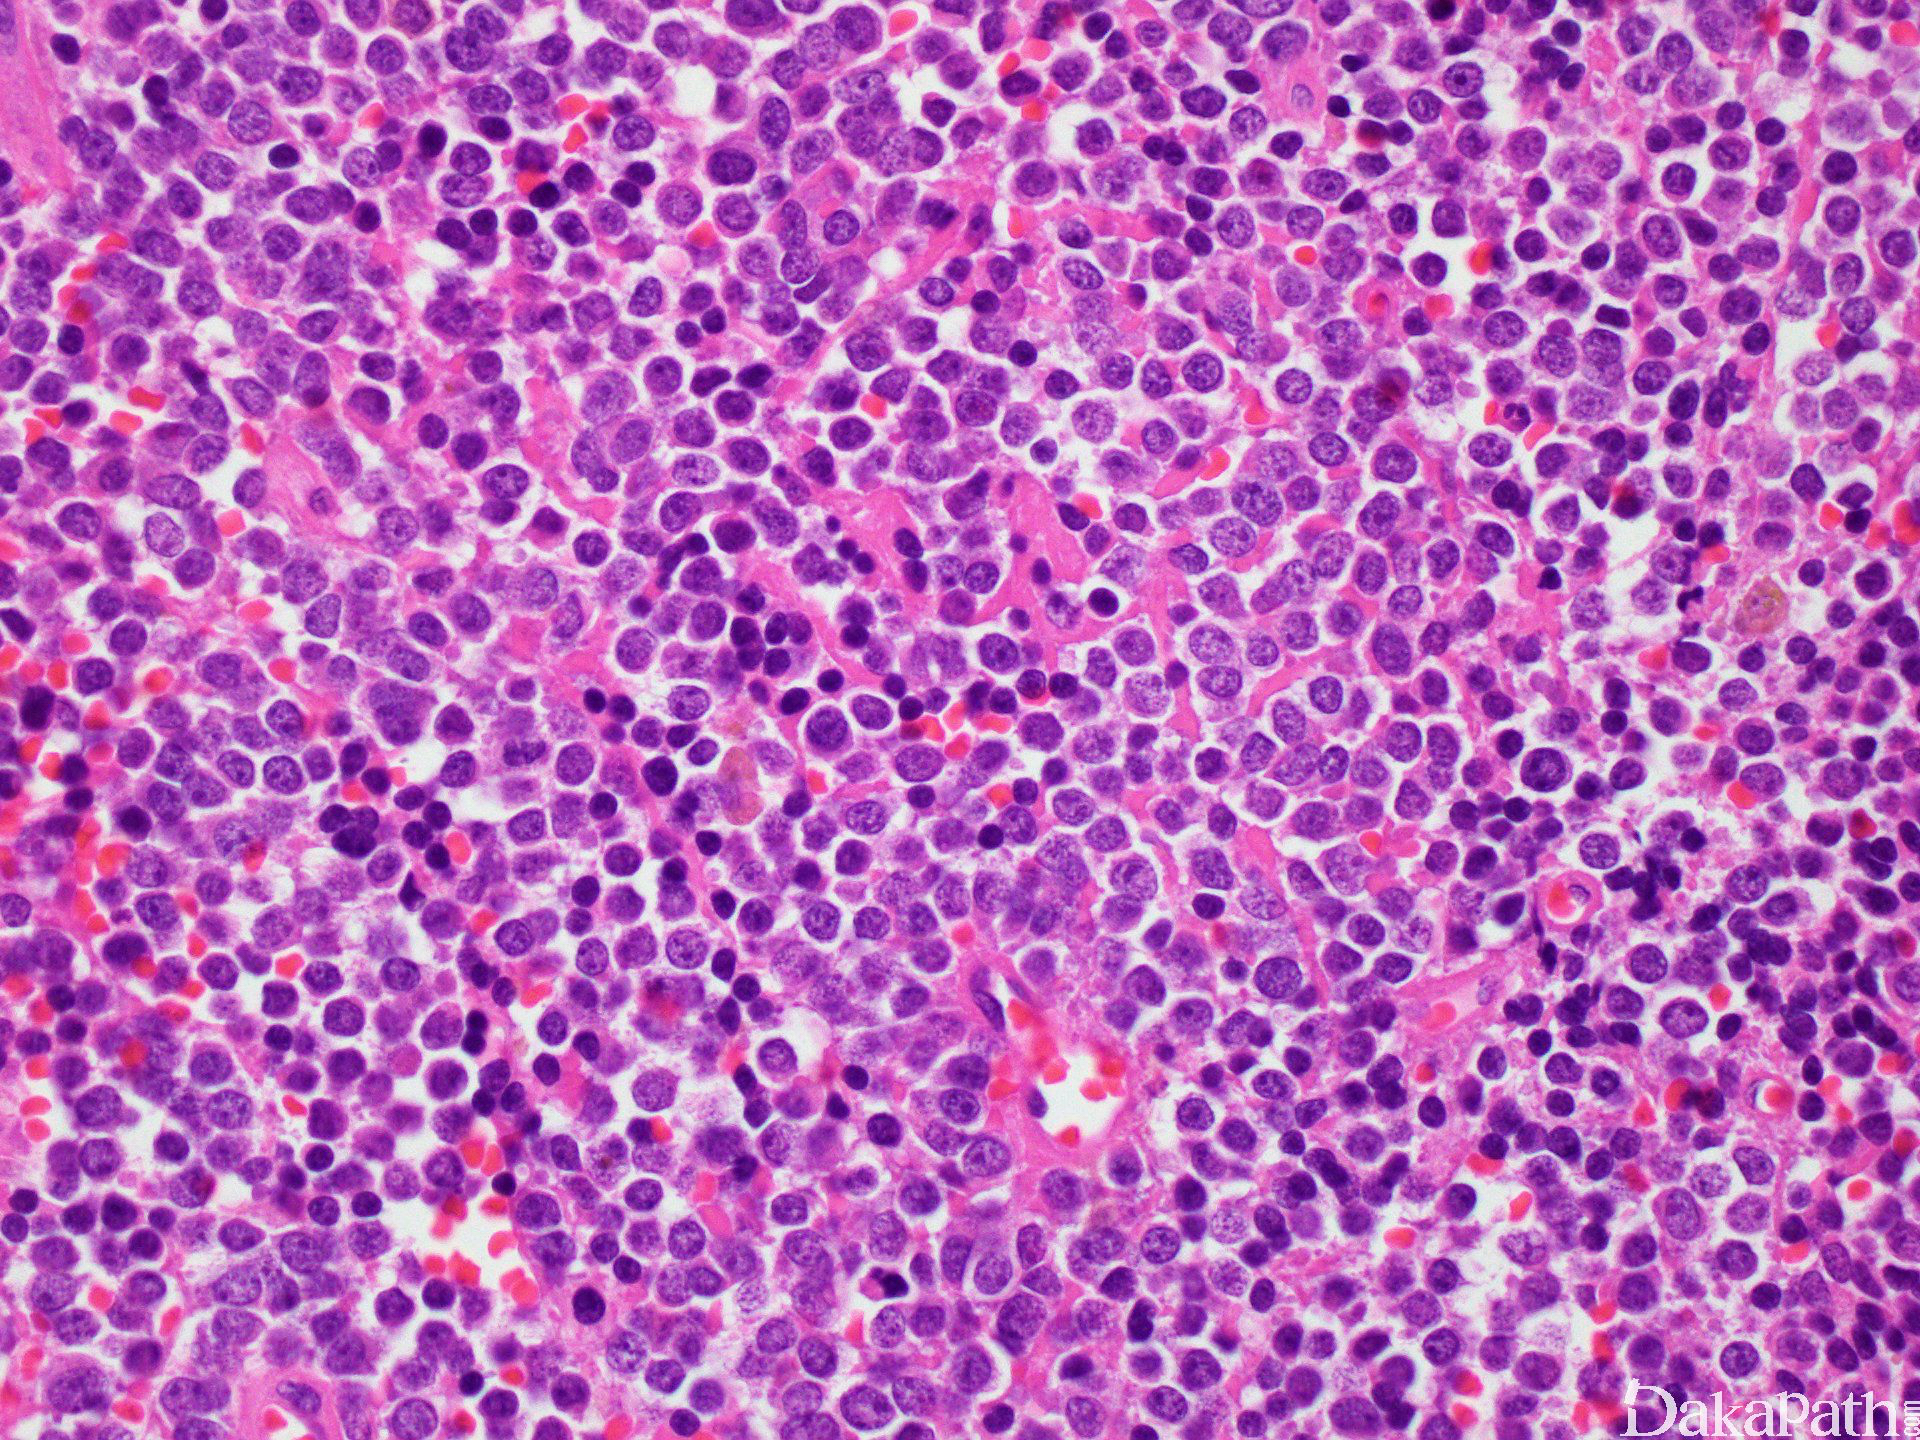

镜下见小圆细胞呈紧密成片或小叶状分布,小叶间为宽窄不等的纤维结缔组织间隔;

细胞胞质稀少或呈不规则小空泡状,PAS 染色阳性,可被淀粉酶消化;核形较规则,圆形或卵圆形,核膜清晰,核染色质细致、均匀,似粉尘样,核分裂像多少不等;部分病例细胞核可不规则,可见核折叠或核沟。

部分病例由小的暗细胞和中等大小的亮细胞混杂组成的双相性形态;暗细胞核深染、胞质稀少,似小淋巴细胞;亮细胞胞质相对丰富淡染,核染色质呈空泡状、似上皮细胞;组织挤压时暗细胞变性、扭曲呈细长梭形,似银丝样镶嵌于亮细胞巢周围,构成银丝状(filigree pattern),该结构常出现在血管丰富的区域或坏死性区域周围;